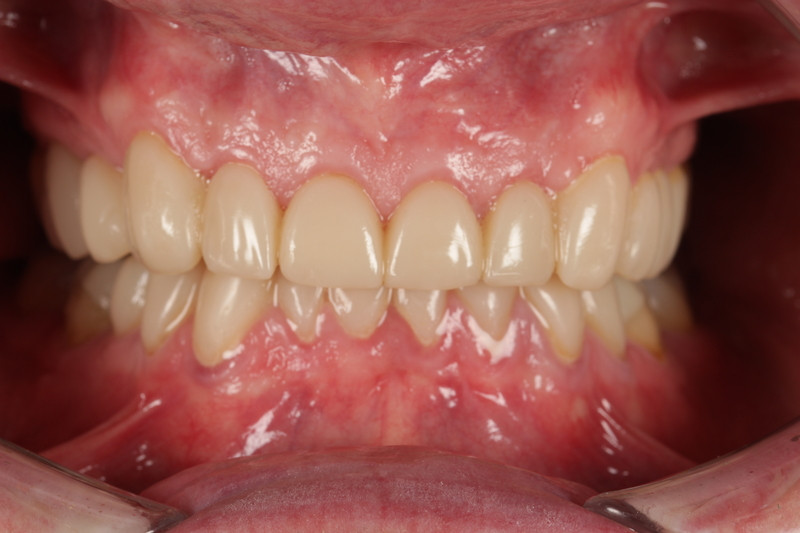

Final outcome

- Patient was extremely happy with the immediate final aesthetic result and reported no issues with adapting to the new OVD and restorations over the subsequent weeks.

- He was reviewed at two weeks, one month, two months and finally three months, and was delighted with no concerns.

Reflection and learning outcomes

Both the team at Avant Garde Laboratories and I are delighted with the result and provide confidence in treating complex cases with 3D Printed materials. The digital design workflow allowed us to be efficient and precise as we were able to share ideas, print models and restorations without delay.

Minimally invasive preparations and biological preservation meant no tooth was prepped into dentine that was already exposed. We managed to preserve significant amounts of enamel for bonding and reducing risk of pulpal flare up.

The case was successful owing to our Patient-centered approach and open communication throughout.

We have incorporated the Sprintray workflow into wear cases for those who seek an affordable solution and aid us in reviewing its performance. Since this case, ceramic dominant resins have been approved for use which will offer stronger restorations and still offer the advantages of repair, accuracy and modification.